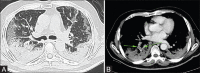

The COVID-19 pandemic began in late December in 2019 and has now reached to 216 countries with 1,08,42,028 confirmed cases and 5,21,277 deaths according to the WHO reports and 6,49,666 confirmed cases in india alone with 18,679 deaths (as on 04th july 2020). RT-PCR has been considered the standard test for diagnosis of COVID 19. However, there has been reported a high false negative rate. This high false negative rate increases the risk of further transmission as well as delays the timely management of suspected cases. We have conducted HRCT chest of various (200 patient case study) proven and suspected cases of COVID-19 infection in the months of April, May and June 2020. Out of 200 scanned patients with clinical complains and suspicion, positive HRCT chest findings were seen in 196 patients, showing clinical-radiological correlation and an accuracy of 98%. The sensitivity of chest CT in suggesting COVID-19 was 98.6% (146/148patients) based on positive RT-PCR results. In patients with negative RT-PCR results and high clinical suspicion, 90% (18/20) had positive chest CT findings. HRCT chest is very sensitive and accurate in picking up lung parenchymal abnormalities in laboratory negative RT-PCR cases with high clinical suspicion of COVID-19 infection and also in all symptomatic patients where RT-PCR was not done. HRCT can also be very sensitive, cost effective and time effective in screening patients with high clinical suspicion. HRCT scores over RT-PCR in giving immediate results, assessing severity of disease and prediction of prognosis. We suggest HRCT chest for detection of early parenchymal abnormalities, assessing severity of disease in all patients with clinical symptoms and suspicion of COVID infection irrespective of laboratory RT-PCR status.